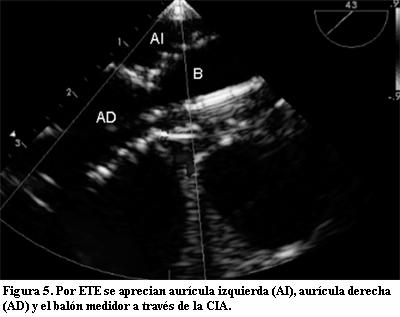

A continuación se coloca balón medidor a través de la CIA procediendo a realizar su insuflación controlado por ETE (figura 5), momento en el cual se hace la medida del defecto estirado que fue de 16 mm (figura 6).

El uso de la ETE juega un importante rol, permitiendo cuantificar el tamaño del defecto, la valoración de los bordes, la relación con estructuras vecinas (vena pulmonar superior derecha, válvula mitral, seno coronario, aorta) medida con balón, despliegue del dispositivo y su liberación (17).